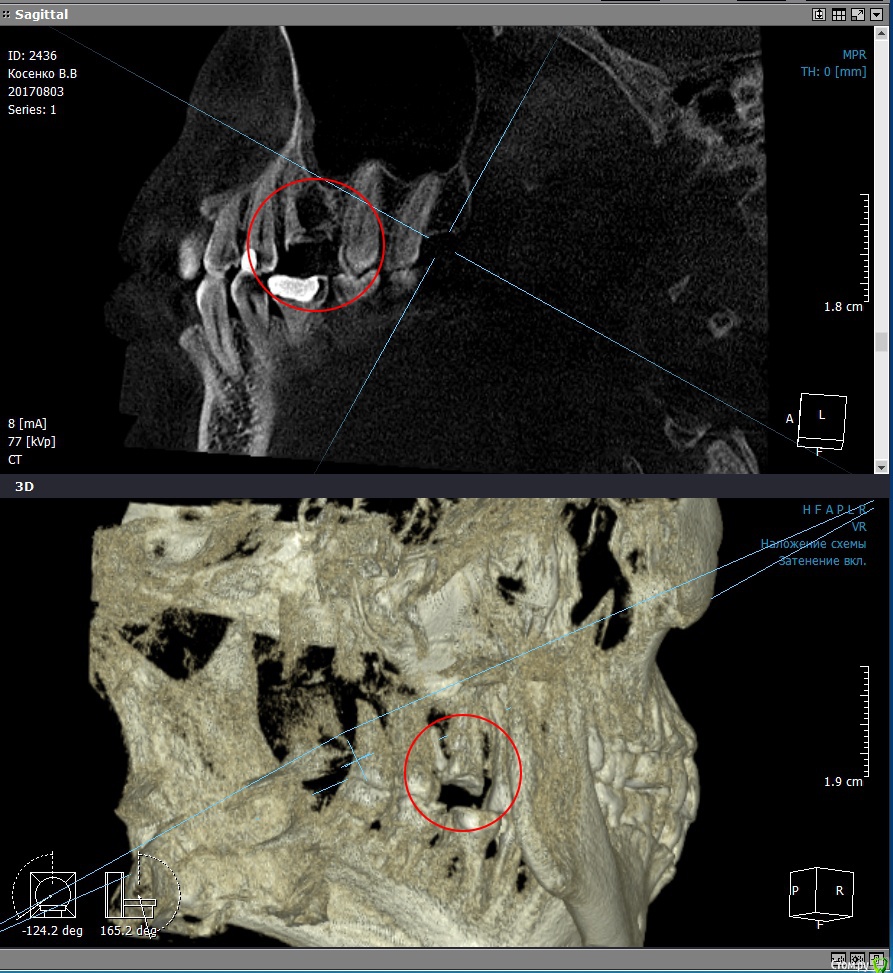

valenkos Опубликовано 20 августа, 2017 Поделиться Опубликовано 20 августа, 2017 Здравствуйте! Уважаемые стоматологи, очень нужен Ваш совет. Над зубом с коронкой появился свищ. Коронку сняла, около месяца ходила без коронки, полоскала водой с солью, свищ не делся. Сделала 3D снимок. Посоветуйте, что делать далее. Вот ссылка на снимок https://fex.net/#!952190258848 Проблемы с верхним угловым зубом с левой стороны. Ссылка на комментарий

valenkos Опубликовано 21 августа, 2017 Автор Поделиться Опубликовано 21 августа, 2017 Сделала скриншоты, пожалуйста, посмотрите Ссылка на комментарий

valenkos Опубликовано 21 августа, 2017 Автор Поделиться Опубликовано 21 августа, 2017 (изменено) Остальные картинки в архиве, так как больше картинок вставить не получаетсяhttps://www.dropbox.com/s/935ee0acbvn775s/Pics.zip?dl=0 Изменено 21 августа, 2017 пользователем valenkos Ссылка на комментарий

Alejandro Опубликовано 22 августа, 2017 Поделиться Опубликовано 22 августа, 2017 Удалять Ссылка на комментарий

red_butler Опубликовано 22 августа, 2017 Поделиться Опубликовано 22 августа, 2017 Удалять Ссылка на комментарий